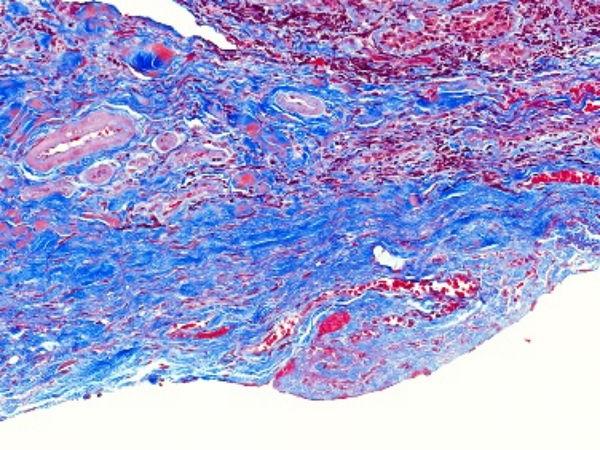

MASSON染色利用不同染料分子與組織結構的相互作用,實現對膠原纖維和肌纖維的精準區分。在染色過程中,肌纖維呈現為紅色,而膠原纖維則呈現為綠色或藍色。這種色彩對比使得纖維組織在顯微鏡下變得清晰可見,醫生能夠清晰地觀察到纖維化的程度和范圍。

圖1. Masson組織染色結果示例(最右列),可看到不同處理條件下膠原纖維(藍色)和肌纖維(紅色)的分布不同